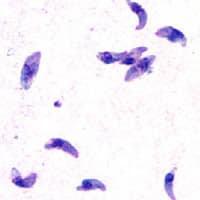

Toxoplasma gondii (ˈtɒksəˌplæzmə_ˈɡɒndi.aɪ,_-iː) is a parasitic protozoan (specifically an apicomplexan) that causes toxoplasmosis. Found worldwide, T. gondii is capable of infecting virtually all warm-blooded animals, but felids are the only known definitive hosts in which the parasite may undergo sexual reproduction. In rodents, T. gondii alters behavior in ways that increase the rodents' chances of being preyed upon by felids. Support for this "manipulation hypothesis" stems from studies showing that T. gondii-infected rats have a decreased aversion to cat urine while infection in mice lowers general anxiety, increases explorative behaviors and increases a loss of aversion to predators in general. Because cats are one of the only hosts within which T. gondii can sexually reproduce, such behavioral manipulations are thought to be evolutionary adaptations that increase the parasite's reproductive success since rodents that do not avoid cat habitations will more likely become cat prey. The primary mechanisms of T. gondii–induced behavioral changes in rodents occur through epigenetic remodeling in neurons that govern the relevant behaviors (e.g. hypomethylation of arginine vasopressin-related genes in the medial amygdala, which greatly decrease predator aversion). In humans, particularly infants and those with weakened immunity, T. gondii infection is generally asymptomatic but may lead to a serious case of toxoplasmosis. T. gondii can initially cause mild, flu-like symptoms in the first few weeks following exposure, but otherwise, healthy human adults are asymptomatic. This asymptomatic state of infection is referred to as a latent infection, and it has been associated with numerous subtle behavioral, psychiatric, and personality alterations in humans. Behavioral changes observed between infected and non-infected humans include a decreased aversion to cat urine (but with divergent trajectories by gender) and an increased risk of several psychiatric disorders – particularly schizophrenia and bipolar disorder.